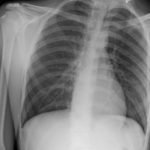

Initial chest radiograph showed a 50% right-sided pneumothorax with no mediastinal shift, which can be identified by the sharp line representing the pleural lung edge (see arrows) and lack of peripheral lung markings extending to the chest wall. While difficult to accurately estimate volume from a two-dimensional image, a 2 cm pneumothorax seen on chest radiograph correlates to approximately 50% volume.1 The patient underwent insertion of a pigtail pleural drain on the right and repeat chest radiograph showed resolution of previously seen pneumothorax. Ultimately the pigtail drain was removed and chest radiograph showed clear lung fields without evidence of residual pneumothorax or pleural effusion.